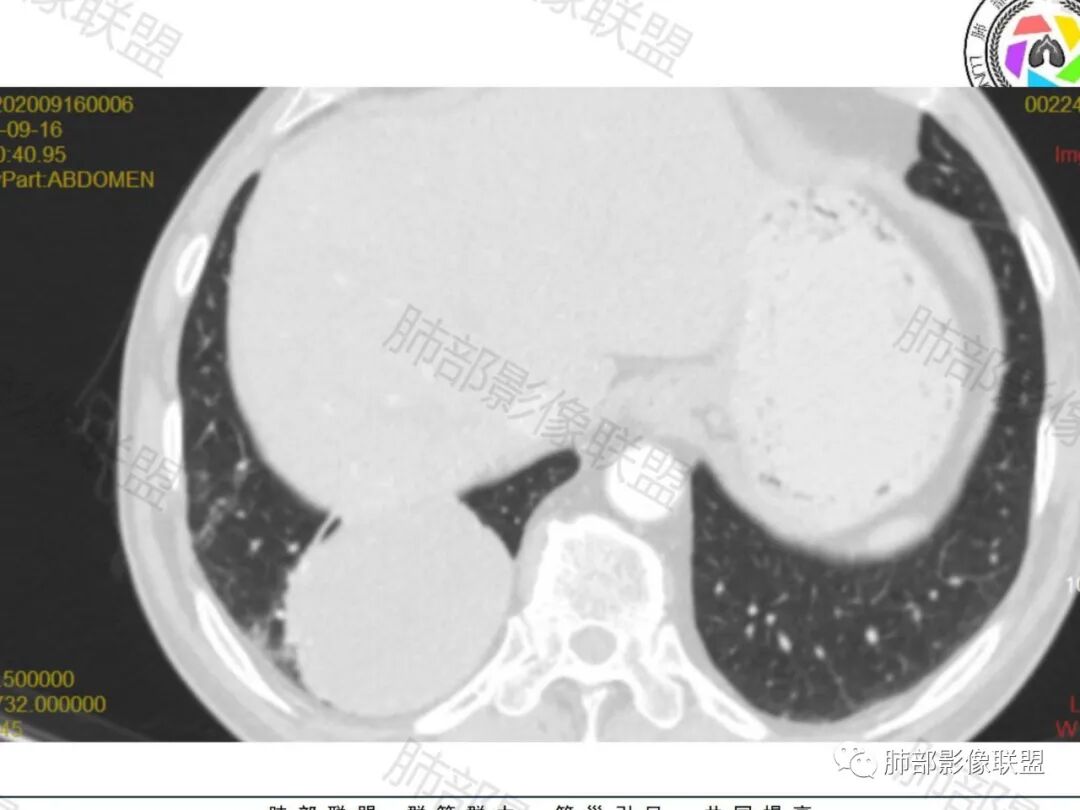

右肺下叶一类圆形肿块影,内缘边缘光滑,外缘边界模糊,可见磨玻璃影,整体以彭隆为主,部分边缘包绕支气管,平扫密度尚均匀,增强后不均匀强化,部分与膈肌黏连,临床,62岁男性,无症状,考虑恶性:腺癌,鳞癌,神经内分泌癌,肉瘤

老年人,偶然发现,右肺下叶类圆形软组织占位,密度较均匀,病灶边缘光滑,无毛刺分叶,支气管血管受挤压向外移位,增强病灶强化较均匀。考虑恶性肿瘤,外向内生长,肉瘤,肉瘤样癌,癌肉瘤,其次神经内分泌癌。

右肺下叶类圆形软组织肿块,病灶边缘光滑,无明显毛刺分叶,支气管受压推移,血管贴边,部分血管进入病灶,增强病灶强化不均匀,内可见低密度,病灶与右侧膈肌分界不清,考虑神经内分泌肿瘤,大细胞癌。鉴别PSP

老年男性,肿瘤标志物高,右肺下叶类圆形肿块,宽基底与胸膜相连,边缘光整,密度均匀,周围气管及血管受压推移,延迟强化,其内见纤细血管,似有小低密度灶,首先考虑间叶组织恶性肿瘤,良性平滑肌瘤、纤维瘤不除外

患者中老年男性,检查发现右下肺占位。查肺癌标记物稍有升高。血常规白细胞计数稍降低。胸部CT:右肺下叶后基底段类圆形肿块,边缘光滑,边界清楚,周边见气管受压扩张,增强轻度强化,内见点状低密度影,见血管贴边。综合考虑良性过低度恶性病变,PSP可能,其它恶性肿瘤待排。

老年男性,检查发现右下肺占位。CT:右肺下叶一类圆形肿块影,膨隆,无分叶,边缘基本光滑,近端支气管推挤狭窄,与胸膜夹角为锐角,增强见不均匀强化,未见坏死,近端见血管贴边,胸壁脂肪间隙清楚。考虑良性病变——PSP可能性大。鉴别神经内分泌癌、肉瘤、SFT。

胸部CT:右肺下叶一类圆形肿块影,边界清楚,大部分边缘光滑、外缘边界模糊,邻近支气管推移、血管贴边,病灶内可见分枝状血管,平扫密度尚均匀,增强后大部分均匀延迟强化,部分与膈肌黏连、尾征?考虑:类Ca>PSP>SFT。鉴别肉瘤样Ca,CD等。